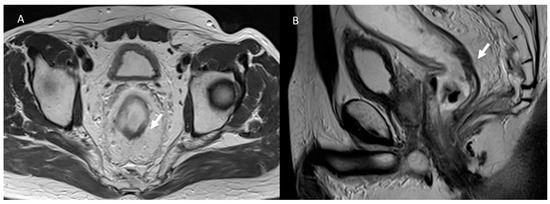

3.2. Fistula